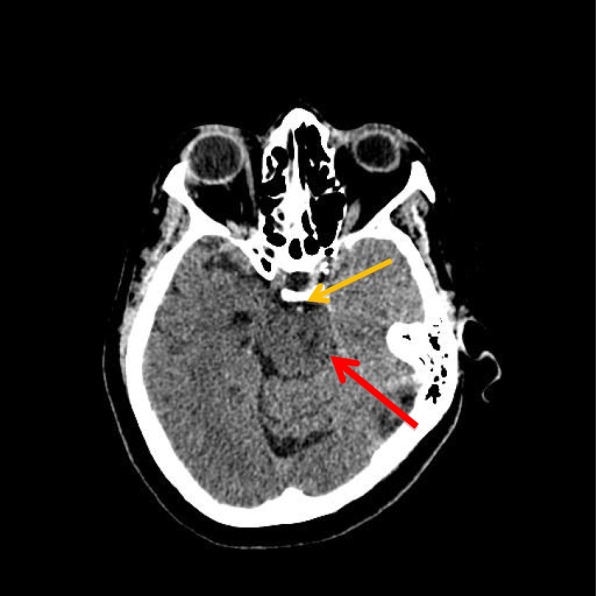

On day 3 of admission, when the patient had been weaned off sedation and paralytic therapy, she demonstrated decorticate posturing, intact gag and cough reflex, positive Babinski reflexes bilaterally, and intact pupillary reflexes. The patient’s motor strength was dramatically decreased in both upper and lower extremities. She was obtunded, unable to follow commands, and opened her eyes spontaneously. On day 4 of admission, she was minimally responsive to commands and was able to communicate only with vertical eye movements. Repeat noncontrast CT showed hyperdensity in the basilar artery, suggestive of occlusion due to thrombosis, which was not present in the initial CT findings (Fig. 1). Findings of lumbar puncture with cerebrospinal fluid examination and electroencephalography (EEG) were unremarkable. MRI showed large foci of abnormally restricted vessels of the brainstem with recent infarction, occurring bilaterally with no observed hemorrhage (Fig. 2). MRA revealed complete loss of flow-related signal within the distal basilar artery (Fig. 3).

Fig. 1.

Axial computed tomography of the patient’s head without contrast from February 7, 2015. Image at the level of the brainstem demonstrates a hyperdense basilar artery (orange arrow), which in the appropriate clinical setting is concerning for occlusion of the basilar artery due to thrombosis. Also, note that the pons (red arrow) is slightly decreased in attenuation compared with the surrounding brain parenchyma, concerning for ischemia. This finding is slightly more prominent on the left side